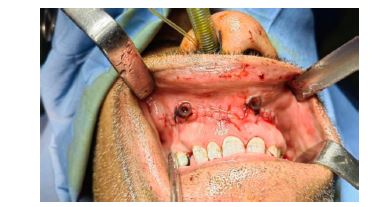

گزارش مورد : بیمار مردی ۵۷ ساله، بدون سابقه بیماری سیستمیک خاص، با شکایت تورم مزمن، بدون درد و با رشد آهسته در ناحیه قدامی ماگزیلا از 1سال گذشته در اسفندماه 1402 به درمانگاه دندانپزشکی مراجعه کرده و پس از بیوپسی و شک به OKC بیمار توسط دندانپزشک به سرویس جراحی دهان و فک و صورت بیمارستان شهید رهنمون یزد ارجاع داده شد. تورم طی یک سال گذشته بهتدریج افزایش یافته بود و با مصرف دارو یا اقدامات دندانی پیشین بهبود نیافته بود. بیمار سابقه ضربه یا جراحی قبلی در این ناحیه نداشت. در معاینه خارجدهانی، تورم غیرقرینه در ناحیه زیر بینی و لب فوقانی مشاهده شد که موجب برهمخوردن خفیف تقارن صورت شده بود. پوست روی ناحیه متورم طبیعی و فاقد تغییر رنگ یا زخم بود (شکل 1و2) (نمای تحتانی صورت نیز برجستگی پایه بینی و ناحیه سابنازال را تأیید کرد. در معاینه داخلدهانی، تورم سفت و بدون درد در مخاط لبی ماگزیلا از ناحیه مولر دوم سمت راست تا مولر دوم سمت چپ دیده شد. مخاط روی ضایعه اندکی قرمزتر از مخاط مجاور بود، ولی زخم، ترشح یا التهاب حاد مشاهده نشد (شکل 3). رادیوگرافی پانورامیک اولیه، ضایعهای رادیولوسنت، تکحفرهای و با حدود مشخص را در ناحیه قدام وخلف ماگزیلا نشان داد که از دندان مولردوم سمت راست تا مولر دوم سمت چپ امتداد داشت و منجر به نازکشدگی قابلتوجه کورتکس قدامی شده بود (شکل ۴). ارزیابی تکمیلی باCBCT، ضایعهای با گسترش وسیع (2*3*4 سانتیمتر) در محور قدامی-خلفی فک بالا را تأیید کرد که بدون درگیری سینوس فکی یا کف بینی بود. دیوارههای استخوانی پالاتال و باکال در محل ضایعه نازک شده اما پیوسته بودند. جابهجایی اندک ریشههای دندانهای مجاور بدون تحلیل ریشه مشاهده شد (شکل 5). با توجه به ویژگیهای بالینی و تصویربرداری، تشخیصهای افتراقی شامل آملوبلاستوما، کیست مجرای نازوپالاتین و OKC مطرح شد. بیوپسی انسیزیونی از ضایعه انجام و نمونه جهت بررسی هیستوپاتولوژیک ارسال شد. گزارش پاتولوژی نشان داد که ضایعه دارای اپیتلیوم سنگفرشی مطبق پاراکراتینیزه با سطح مواج و چینخورده، بدون رتپگ، و لایه بازال نردبانی با سلولهای استوانهای پلاریزه است. کراتین فراوان در لومن مشاهده شد و میتوز در لایههای بازال و پارابازال وجود داشت. این ویژگیها با تشخیص OKC نوع پاراکراتینیزه مطابقت داشتند (شکل 7). با توجه به محل ضایعه، اندازه نسبتاً بزرگ آن، و نزدیکی به ساختارهای حیاتی مانند حفره بینی و قاعده سینوس، تصمیم به انجام درمان مرحلهای گرفته شد. در مرحله اول، مارسوپیالیزاسیون تحت بیهوشی عمومی با اینتوباسیون نازال انجام شد. برش وستیبولار دوطرفه در قدام ماگزیلا ایجاد و پس از بازکردن دیواره کیست، دو عدد درن نلاتون در طرفین ضایعه قرار داده شد. بخیه لبههای مخاطی به دیواره کیست با نخ سلیک ۰-۲ انجام و مخاط با ویکریل ۰-۳ سوچور شد. شستشوی کامل با نرمالسالین انجام شد و پانسمان داخل حفره با گاز استریل صورت گرفت (شکل 8). تا زمان حضور بیمار در بیمارستان شستشو توسط پزشک انجام شد و نهایتا پس از آموزش شستشو به بیمار و اطمینان از آموزش وی بیمار مرخص گردید. در پیگیریهای انجام شده در فواصل دو هفته، یک ماه، سه ماه و شش ماه، بیمار بدون علائم عود، درد یا ترشح باقی ماند. تورم بهتدریج کاهش یافت و نمای مخاطی ناحیه به وضعیت نرمال نزدیک شد. گرافی پانورامیک پیگیری شش ماهه کاهش چشمگیر اندازه ضایعه و افزایش تراکم استخوان را نشان داد (شکل 9). با توجه به پاسخ مناسب ضایعه به مرحله اول درمان، برنامهریزی برای انجام انوکلیشن تأخیری به همراه برداشت محیطی (Peripheral Ostectomy) پس از شش ماه انجام شد. در مرحله دوم تحت بیهوشی عمومی، با ایجاد یک برش وستیبولار و نمایان شدن ناحیه ضایعه، پوشش ضایعه از دیوارههای استخوانی جدا گردید. بهمنظور برداشت استخوان مجاور پوشش کیستیک، از فرز جراحی استفاده شد. پس از انجام انوکلیشن، حفره با ژلفوم پر گردید و برشها با نخ بخیه ۴-۰ پرولن بسته شدند. هدف از این اقدام، حذف کامل اپیتلیوم باقیمانده و کاهش خطر عود ضایعه در بلندمدت خواهد بود.

شکل 4: نمای پانورامیک قبل از انجام مارسوپیالیزاسیون که ضایعه رادیولوسنت تکحفرهای در ناحیه قدامی و خلفی ماگزیلا را نشان میدهد. محدوده ضایعه از مولردوم راست تا ناحیه مولردوم چپ امتداد دارد و نازکشدگی کورتکس قابل مشاهده است.

شکل8: نمای داخل دهانی حین جراحی مارسوپیالیزاسیون در ناحیه قدامی ماگزیلا. دو پنجره در دیواره ضایعه ایجاد شده و توسط بخیه به مخاط دهان متصل شدهاند. پانسمان داخل حفره پس از عمل انجام شده است.